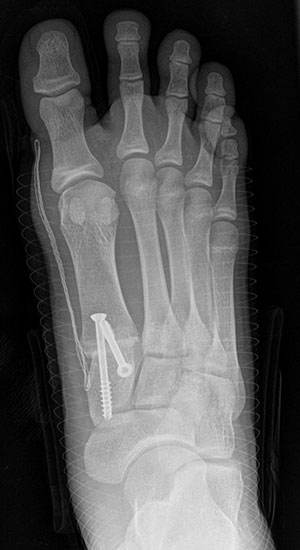

Bezüglich der Operationstechniken wird von früher häufig durchgeführten alleinigen Weich­teileingriffen am Großzehengrundgelenk aufgrund hoher Rezidivraten abgeraten 15. Die Operation nach Mc Bride mit lateralem Release, Exzision des lateralen Sesambeins, Abtragen der Pseudoexostose, Sehnenetransfer des M. adductor hallucis und mediale Kapselraffung zeigte unbefriedigende Mittel- und Langzeitergebnisse 16. Die Cerclage fibreux (mediale Kapselraffung) und das laterale Kapselrelease wird heute in Kombination mit einem knöchernen Eingriff angewendet. Bezüglich des Einsatzes von minimalinvasiven Operations­techniken vor Wachstumsabschluss liegen bisher keine Daten vor. Alle Osteotomien lassen sich nach Bedarf miteinander kombinieren. Es ist darauf zu achten, dass Osteotomien keine offenen Wachstumsfugen verletzen.

• Medial zuklappende Grundphalanxosteotomie nach Akin 17

• Subcapitale distale Chevron Osteotomie nach Austin 18

• Diaphysäre Osteotomie

• Scarf 19

• Ludloff 20

• Proximale Metatarsale I Osteotomien 21

• medial aufklappend – verlängernd

• lateral zuklappend – verkürzend

• bogenförmige Crescentic Osteotomie

• proximale Chevron Osteotomie

• proximale Verschiebeosteotomie

• medial aufklappende Cuneiforme I Osteotomie 1522

• Wachstumslenkung: Hemiepiphysiodese der lateralen Basisfuge am Metatarsale I  23

• Nach Schluss der Wachstumsfugen: TMT I Arthrodese nach Lapidus 2425